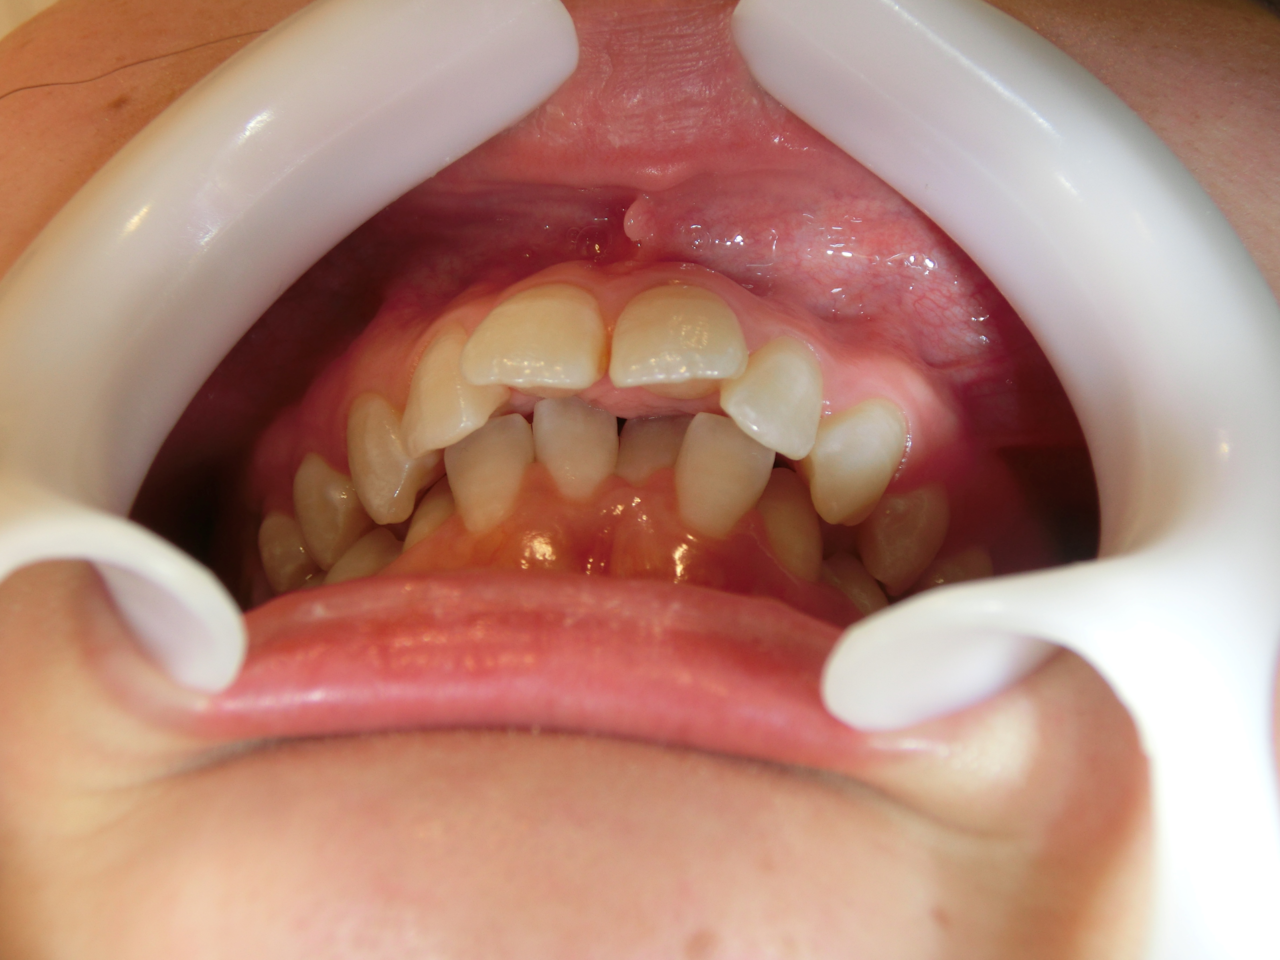

症例写真②

矯正前(正面)

矯正後(正面)

こちらの患者さまは、上下の前歯が離れていて、奥歯でしか噛めない「開咬(かいこう)」という状態でした。先天的な理由の場合もありますが、舌の癖や口呼吸などの悪い癖が原因でこのような歯並びになってしまいます。矯正後は、見た目が良くなっただけではなく、前歯でもしっかり食べ物を噛み切れるようになりました。

治療説明 歯科矯正でも目立ちにくい矯正方法です。透明に近いマウスピース型の矯正装置(アライナー)のため、歯に装着しても目立つことなく歯並びを矯正することが出来ます。また、一人ひとりの合わせて矯正装置を作製いたします。

治療期間 1年1か月

治療費用498000 円

治療の副作用(リスク)歯の動き方には個人差があり、予想された治療期間が延長する可能性があります。治療中は矯正歯科装置をつけるためハミガキを適切に行ってお口の中を常に清潔に保ち、さらに、かかりつけ歯科医に定期的に受診することが大切です。マウスピースの使用状況、定期的な通院など、矯正歯科治療には患者さんの協力が必要であり、それらが治療結果や治療期間に影響します。治療の経過によっては当初予定していた治療計画を変更する可能性があります。保定装置の装着時間が十分確保できない場合、歯並びや、咬み合せの「後戻り」が生じる可能性があります。